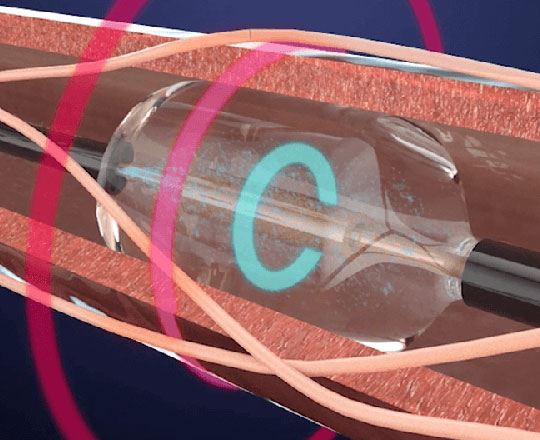

El dispositivo Conformal (Conformal Medical, Estados Unidos) está diseñado para adaptarse a la anatomía de la orejuela de cada paciente y disminuir la necesidad de ecografías transesofágicas y anestesia general durante el implante.

Tiene un esqueleto de nitinol con dos filas de 20 anclajes que se fijan a la pared de la orejuela, con un recubrimiento matricial de espuma en forma de tapón. En la parte superior de este, la expuesta al contacto sanguíneo, lleva un recubrimiento con tejido de politetrafluoroetileno expandido (ePTFE) que evita la trombosis del dispositivo1.

La matriz de espuma permite sellar con mayor eficacia posibles fugas de otros dispositivos, y se adapta a la mayor parte de anatomías de la orejuela con solo dos tamaños. La gran ventaja del recubrimiento de ePTFE es que reduce de manera importante la formación de trombos sobre el dispositivo, sobre todo cuando la anticoagulación o la antiagregación están contraindicadas.